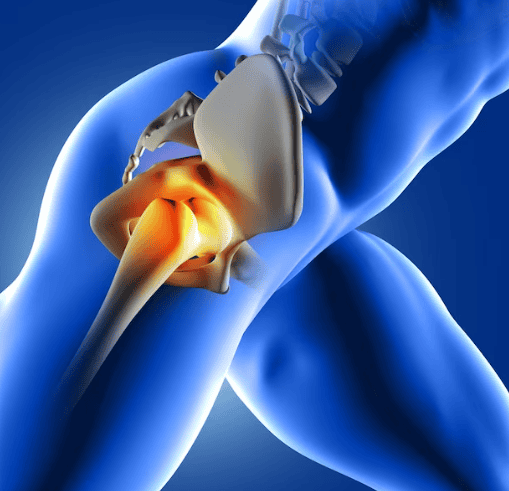

SI una cosa clara tenen els pacients sotmesos a una artroscòpia de maluc, és que el dolor després d’aquesta intervenció no se’n va i fins i tot pot reaparèixer. És el mateix que tenien abans d’operar-se.

Segurament que la cirurgia a la qual han estat sotmesos ha millorat l’estat del seu maluc, però el pacient té un dolor que no els hi permet fer la seva vida normal. Ni caminen amb normalitat, ni poden pujar costes, ni conduir massa estona, asseguts en un lloc una mica baix, no ho toleren, o quan comencen a córrer han d’aturar-se.

Problemes musculars que afecten la recuperació

És molt freqüent que no existeixi una lesió a l’articulació. La major part de les vegades són els músculs, els tendons que no arriben a tenir la suficient força o elasticitat per tornar a funcionar bé.

El psoes i el recte femoral, els músculs que flexionen el maluc, necessiten tenir tanta força com suficient elasticitat per generar un moviment i una potència que ens permeti pujar un escala. I són els mateixos músculs que durant mesos no han treballat normal perquè el dolor de maluc no els hi deixava estirar-se amb normalitat.

És freqüent que les primeres setmanes, mentre es va crosses i el nivell no és molt exigent, no es noten, però quant a deixem les crosses i demanem més treball al nostre maluc, aquests dolors tornen a aparèixer i es disparen.

Dolor a la zona del gluti major: causes i solucions

Altra zona on sovint es té dolor després d’una artroscòpia de maluc és en mig de la natja. Aquí és on està el gluti major. És el múscul que ens permet caminar, pujar escales, o ajupir-nos d’una cadira.

Quan hi ha problemes de maluc aquest múscul perd força i triga mesos a recuperar-se. Com aquestes activitats les iniciem de seguida i el ritme de recuperació muscular és més lent que la nostra progressió, apareix dolor al mig de la natja. Com un ganivet que es clava. S’ha de treballar el múscul perquè el dolor desaparegui.

¿Quan hem de preocupar-nos del dolor articular?

El dolor després d’una artroscòpia de maluc que hauria de preocupar-nos més seria el dolor persistent a l’engonal. Aquell dolor que ve des del maluc, des de l’articulació. Si es manté el dolor, a aquesta zona, podem tenir un problema per diverses causes.

La més preocupant és que la cirurgia hagi estat insuficient. Quan la cirurgia rebaixa us satura el làbrum (fibrocartílag que cobreix l’os acetabular) i el podem fer curt. La por de ser massa agressius els pot portar al fet que existeixen zones on no s’hagi resolt el pinçament. I com el làbrum pot patir les conseqüències, pot tornar-se a rompre, I això, a vegades obliga, a tornar a passar pel quiròfan.

Dolor a l’engonal: possibles complicacions i causes

Si el problema inicial no fos solament el pinçament i tinguem un cert grau d’artrosi, la rigidesa associada pot empitjorar i totes les estructures de parts toves poden reduir-nos la mobilitat del maluc i augmentar el dolor.

Malgrat que hi hagi un aspecte radiològic bo, el dolor i la falta de mobilitat poden portar-nos a fer altra cirurgia. En aquest cas, podem plantejar-nos repetir l’artroscòpia o fins i tot canviar a una pròtesi de maluc.

Quan optar per una segona intervenció

Quan el dolor després d’una artroscòpia de maluc, persisteix, és clar que aquesta cirurgia no va ser la millor solució. Sobretot, si la nova cirurgia es planteja a menys de dos anys després de l’artroscòpia. En moltes ocasions és obvi que els pacients no milloraran amb una artroscòpia i es decideix directament a una pròtesi de maluc.

Però no sempre és tan fàcil. Pacients joves, amb un lleu desgast, alguns canvis degeneratius, poden fer-nos dubtar si encara podem ajudar-los amb una tècnica que conservi el seu maluc o directament optar per una major agressivitat, sacrificar el seu maluc i entrar en el món de les pròtesis de maluc.

Beneficis i riscos d’una pròtesi de maluc

Com veurem més endavant, la pròtesi de maluc no és la solució definitiva i totalment segura, sinó que tenim uns problemes que afortunadament són poc freqüents però devastadors pels pacients.